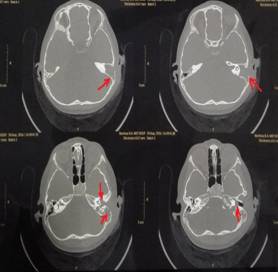

該患兒既往無中耳炎及耳流膿病史,僅表現(xiàn)為1個(gè)月前耳后稍有紅腫、疼痛,在當(dāng)?shù)蒯t(yī)院曾被診斷為“蚊蟲咬傷”所致,家長(zhǎng)也未引起足夠的重視。近半月來,患兒耳后紅腫疼痛加重,遂到我市某三甲醫(yī)院就診,行高分辨率中耳乳突CT,發(fā)現(xiàn)側(cè)顱底、中耳乳突腔巨大新生物占位,乳突骨皮質(zhì)破壞吸收,并可疑耳后骨膜下膿腫形成。病情若進(jìn)一步發(fā)展,膽脂瘤破壞顱底骨質(zhì),將極有可能并發(fā)腦膜炎、腦膿腫,甚至出現(xiàn)敗血癥、腦疝等,危及生命。

1.術(shù)前耳后紅腫 2.術(shù)前CT1